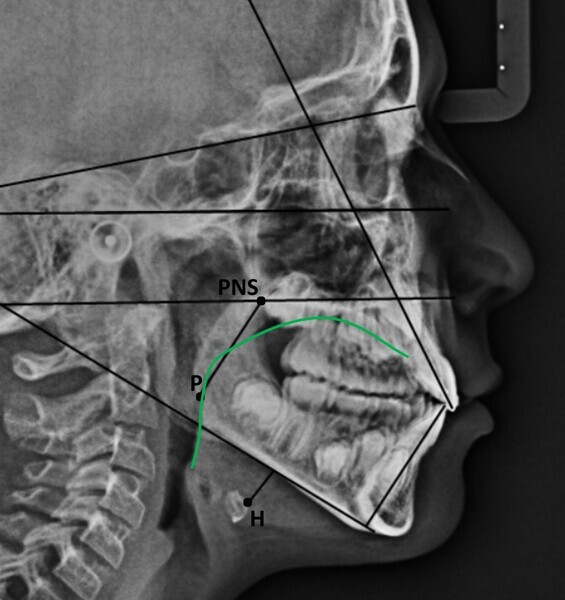

In my clinical practice, I prevent patients from rolling and rotating their heads using a cephalostat while allowing pitching: only after they have positioned themselves comfortably, do I place the post on the nasion, without exerting pressure. In this way, the patient will assume his or her habitual posture, and this too will be investigated by us. The cephalometric radiograph showed very important dysfunctional aspects (Fig. 4). Antero-rotation of the head and cervical hyper-lordosis were evident. Tracing of the tongue23 showed a very low position of the anterior part, as was found clinically. Cephalometric analysis was performed using the OrisCeph Rx1 CE program (Version 7.70; Elite Computer Italia). The patient showed a Class I skeletal pattern with antero-rotation of the maxillary plane, proclination of the mandibular incisors and increased anterior lower face height.

In the control cephalometric radiograph, the lingual position had completely regularised, the body and tip being in contact with the hard palate, creating an average overbite (Fig. 14). The cervical hyper-lordosis was moving towards correction and the skull posture was less forward.

Functional cephalometric analysis showed clear improvements too (Fig. 15; Table 1). The maxillary plane, which indicates the orientation of the maxilla, had undergone regularisation in both the angle with the skull base (SN line; going from a value of 7.7° at T0 to one of 11.2° at T1) and the angle with the Frankfort plane (going from a value of −2.9° at T0 to one of 0° at T1). The inter-incisal angle had increased, indicating an improvement in the inter-incisal ratios. The excessively divergent angle between the maxillary plane and the mandibular plane had decreased, and the facial divergence regarding both the mandibular angle and the face height index showed remarkable normalisation. Of note, was the reduction in proclination of the mandibular incisors, which went from a mandibular incisor to mandibular plane angle of 96.8° to one of 92.1°.

In agreement with Yoon et al.,4 in the radiographs at T0 and T1, we also calculated the length of the soft palate because its increase in size, as far as we know, is considered a risk factor for the development of obstructive sleep apnoea, and its reduction is part of the therapeutic goals of myofunctional therapy for the treatment of obstructive sleep apnoea.28, 29 The P–PNS value had decreased from T0 (30.0 mm) to T1 (29.4 mm). Also in agreement with Yoon et al.,4 we also calculated the length of the perpendicular from the hyoid bone to the mandibular plane. An increase indicates a low tongue posture. This line had fallen from T0 (16.3 mm) to T1 (11.9 mm), giving further confirmation of improved lingual posture.